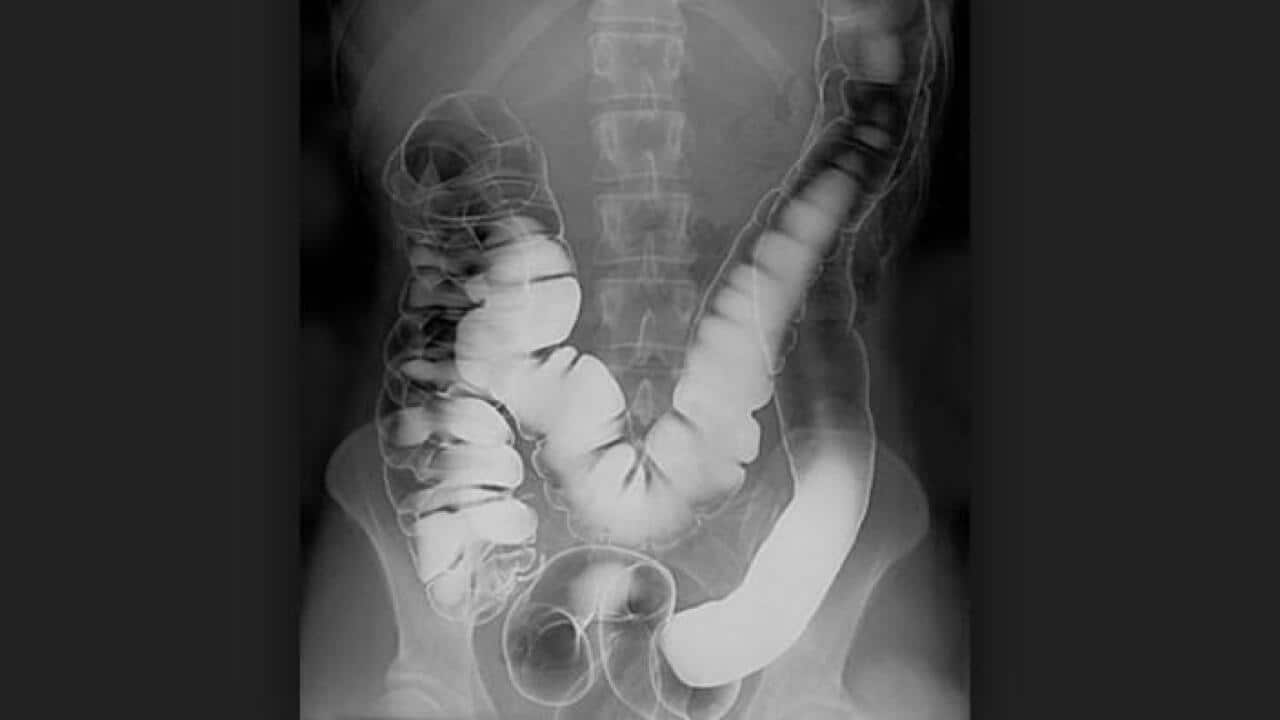

便秘通常是指排便習慣岀了問題。一般定義,是指成年人的排便每周平均少於3次,糞便質量異常,太硬或太小,或是很困難排便。為了改善便秘問題,調整飲食餐單是最有效解決方法。今日介紹有機會導致便秘的八種食物。